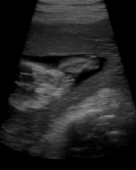

Die räumliche Auflösung des Herzens bei gängigen in-vivo Ultraschall Anwendungen ist aufgrund von Bewegungsartefakten und Positionierungsfehlern momentan noch stark begrenzt und nur von eher geringem diagonistischem Nutzen. Darüber hinaus ist es technisch unmöglich alle medizinisch relevanten Daten des Herzens von einer einzigen Schallkopfposition her zu akquirieren.

Aus diesem Grund werden die Daten bei der bestens bekannten 2D-Untersuchung von verschiedenen Schallfenstern her aufgenommen. Der hier verfolgte Ansatz verbindet die Daten von verschiedenen Schallfenstern auf intelligente Weise. Die Bewegungen des Schallkopfs werden dabei von einem 6DOF Positionsgeber gemessen, wodurch eine absolut freie Positionierung des Schallkopfs ermöglicht wird, und somit für jede zu schallende Region die beste Einschallrichtung verwendet werden kann. Die so aufgenommenen Daten werden bezüglich ihrer inhärenten Bildqualität geprüft und dem entsprechend bei der Komposition verwendet. Durch diese Technik wird der Einfluß von Artefakten derart reduziert, daß die Gesamtqualität des Datensatzes erkennbar gesteigert wird.